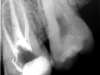

Conservativa: rilevamento della carie, anche con radiografia digitale o con strumento laser, ripristino della morfologia dentale in materiale estetico.

Endodonzia: rimozione della polpa dentale (nervo) dalla camera pulpare e dalla radice dentale e sigillatura con materiale inerte.